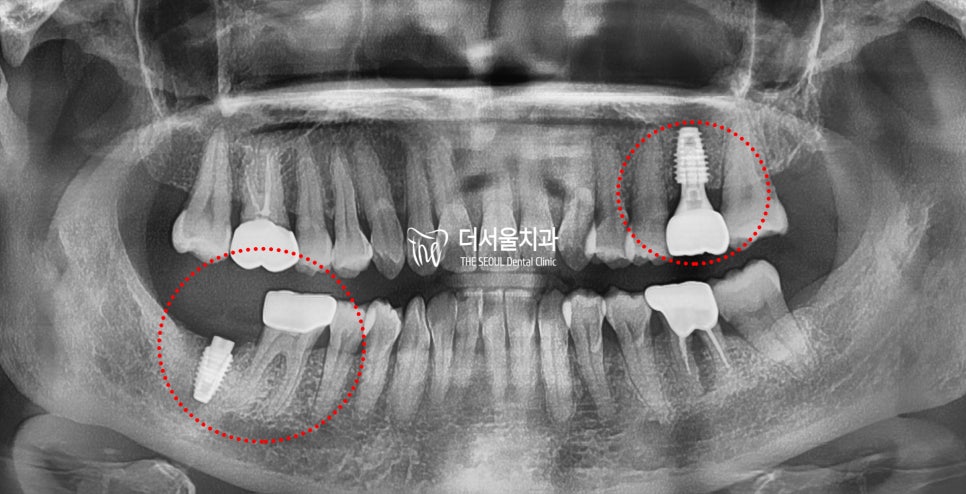

이후 정해진 식립 위치에

픽스쳐를 심어드리고

심한 충치가 나타났던 곳에는

신경치료를 통해 감염된 곳을

깨끗하게 제거해 드렸습니다.